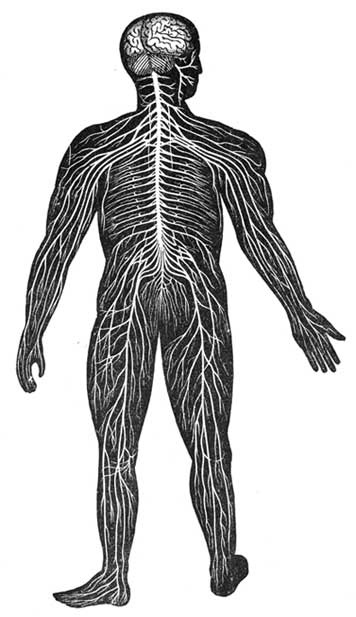

Ankle Swelling.—When long continued in connection with disease or accident, this sometimes leads to a partial withering of the limb up to its very root. In such a case it is best to deal first with the roots of those nerves which supply the limb, which are, in the case of the legs, in the lower part of the back. It is important to apply light pressure to these roots by gently squeezing the muscles of the lower back. This raises a feeling of gentle heat, which slowly passes down the limbs even to the toes. Then the gentle pressure and squeezing must be carried all down the limb, avoiding any degree of pain, until all its muscles have had their share. While progressing down the limb with his rubbing, let the rubber be careful that the individual strokes of his hands be upwards, towards the hip. The blood will thus be propelled towards the heart, while the stimulus of rubbing is conveyed along the nerve trunks towards the foot. The squeezing should be done with a grasping movement of the hands, the limb being held encircled in both hands, thumbs upwards. Warm olive oil is used in this squeezing, and also, if the skin be hard and dry, soap lather (see Lather).

Treatment may also be given for lack of assimilative power. The back, especially on either side of the spine, is rubbed with gentle pressure and hot olive oil. This pressure is so applied that a genial heat arises along the whole spinal column. This done twice a day, for half-an-hour at a time, and continued for several weeks, will markedly restore assimilative power. Cases which have been perfectly helpless for eight and even ten years are cured by this simple method, sufficiently and carefully followed.

An attack of this may often be relieved by rubbing, with the points of the fingers chiefly, gently yet firmly up and down each side of the spine, close to the bone. Even rubbing above the clothing will frequently relieve. The roots of the nerves supplying power to the breathing muscles lie just on each side of the spine, and this kind of rubbing stimulates these roots. It is not rubbing of the skin or backbone which is wanted, but such gentle treatment of the nerve roots on either side of the bone as makes them glow with genial warmth. This rubbing is of course better done on the surface of the skin. See that the patient is warm, then dip the fingers in cold water, and rub as directed. When the water makes the patient feel chilly or he tires of it, use fresh olive oil, warmed if necessary. Avoid all alcoholic drinks, which simply rob the nerves of the very power needed for cure. Temporary relief may be given by such drinks, but it is at the expense of lowered life and reduced chances of recovery.

Back Failures.—Often a severe pain in the toe, foot, ankle, or lower leg has its cause, not in anything wrong with the part which is painful, but in some failure of nerve in the patient's back. Blistering or other treatment of the painful part will often injure, and cannot do much, in any case, to cure. Pains even in the knee and groin sometimes have the same cause—in back failure. In other cases the symptoms are, weariness, stiffness, inability to stoop, or stand long without support, and pains in the stomach and thighs.

In the case of pains in the arms or hands, the upper part of the back is indicated; in leg and foot troubles, the lower part. Neuralgic pains are almost always of this class.

In any case of this kind, heat may be applied to the spine, and rubbing with hot oil given to it, at its upper or lower part as required. If the heat and rubbing increase the pain, then cold applications may be used. Sometimes heat and cold may be needed alternately; but common sense must guide, and all irritation or chilling of the patient must be carefully avoided.